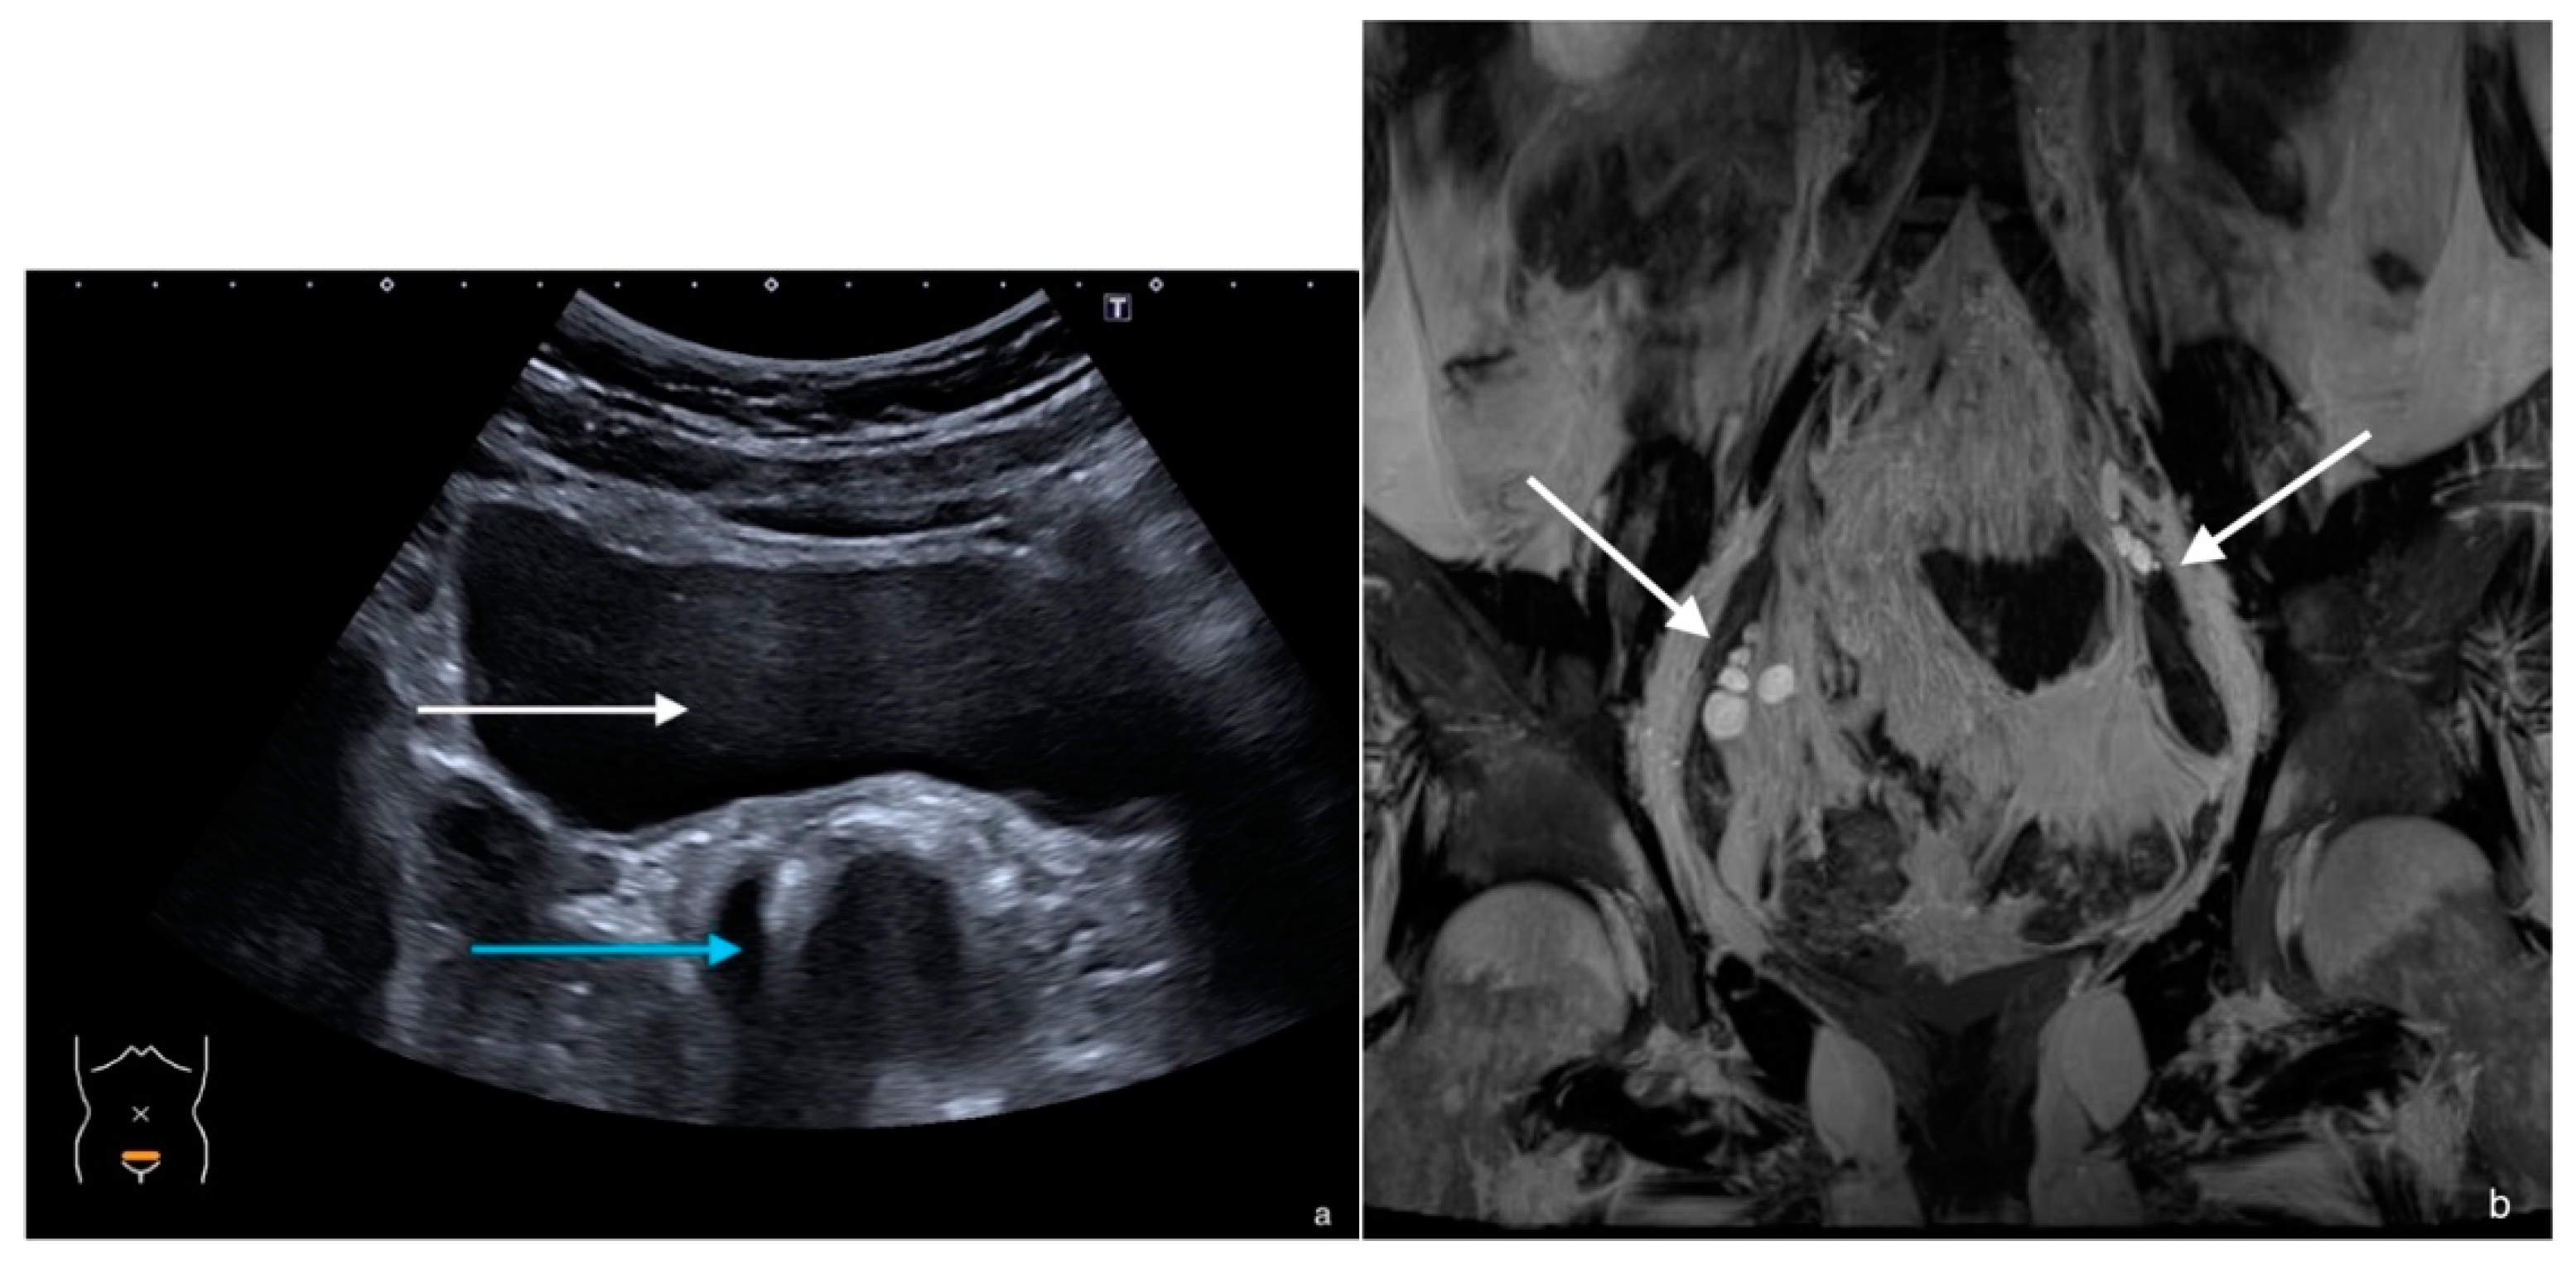

3. Case 2

| MRI report on primary investigation | Absent uterus, impression of hypoplastic vagina. Normal multicystic ovaries | Absent uterus and presence of a short vagina. Normal ovaries | Normal multicystic ovaries and a small uterus of 2.3 × 1.3 cm, described as rudimentary uterus | |

| MRI after referral | Lipofibromatous tissue at location of the uterus, no endo- myometrial or cervical structures. Normal multicystic ovaries | Underdeveloped Müllerian structures. Gonads with (ovo)testicular aspect | Small uterus with normal endo- and myometrial tissue, normal multicystic ovaries | |